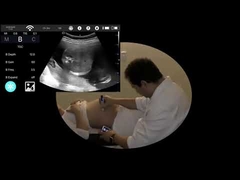

Kalite Portatif Ultrason tarayıcı, taşınabilir ultrason tarayıcı manufacturer from China